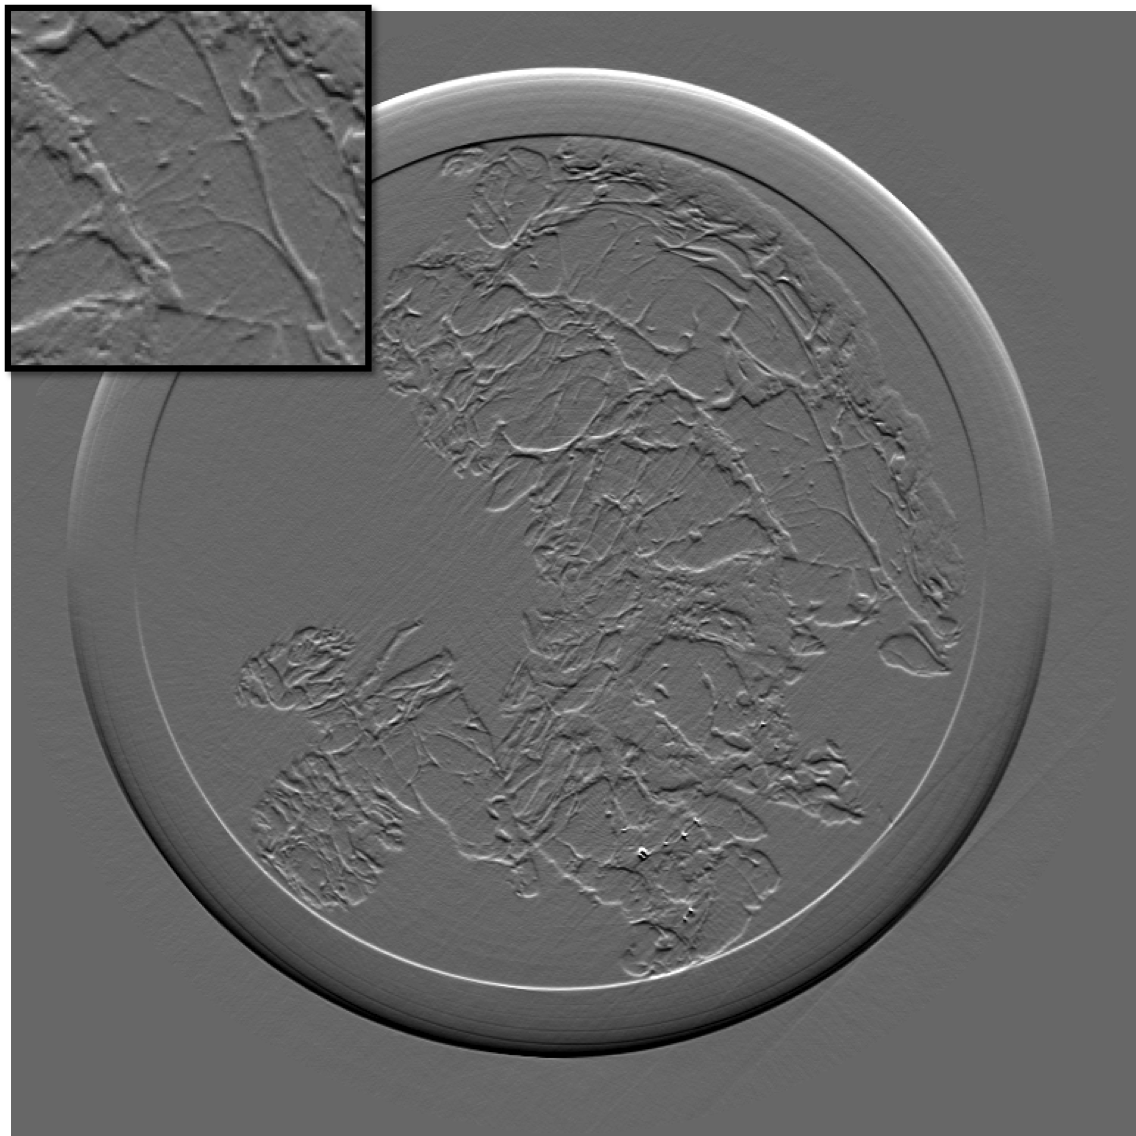

Figure 10 is the reconstruction for a pixels slice, using only 200 projections over the 1000 available. The upper left square is a zoom in the region marked in sub figure 10. The right column is the reconstruction with our method for X and Y components, while the left column is reconstructed with standard filtered back-projection using all 1000 available projections. Using our method we can still generate a high quality image with only one fifth of the projections which would be otherwise necessary to generate a high quality reconstruction with the standard FBP method. Visually the difference between the FBP results obtained with full data set and our method with a five-fold reduction of data is barely noticeable. The different borders of structures like skin layers, fatty tissues, and collagen strands are easily identified. The obtained result are very promising and a systematic evaluation for clinical application is under-way. The radiation dose absorbed by the sample during 200 projections is comparable to that of a standard clinical dual view (2D) mammography (3.5mGy).

For an eventual future clinical application of the PCI method it is important to investigate which is the acceptable compromise in terms of low dose and sufficient level of image quality. We need therefore to better explore how the quality of the reconstruction is degraded when we reduce the dose (i.e. number of projections and the acquisition time) further below the standard values. To this end, we performed a reconstruction with only 125 projections and results are shown in the figure III-D for one gradient differential image.

For an eventual future clinical application of the PCI method it is important to investigate which is the acceptable compromise in terms of low dose and sufficient level of image quality. We need therefore to better explore how the quality of the reconstruction is degraded when we reduce the dose (i.e. number of projections and the acquisition time) further below the standard values. To this end, we performed a reconstruction with only 125 projections and results are shown in the figure11. The first column present the result using our method, the second column is the result of reconstruction using FBP algorithm.

If a slightly higher noise level is tolerable, the method may be used with very few projections and thus applied to the screening and diagnosis of human breast cancers with an even lower radiation dose than conventional dual mammography. The results of our reconstruction show an image quality and a capability of discriminating fine structures that are still clinically acceptable. On the contrary, images produced with the standard FBP reconstruction method are very noisy and not diagnostically satisfactory.